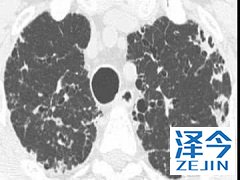

患者使用尼达尼布会产生较强的副作用吗 尼达尼布治疗特发性肺纤维化的作用已经得到了FDA的认可,并且已经批准上市。通过降低患者的用力肺活量来改善患者的肺功能,并且维持在一个比较稳定的状态,与使用安慰剂的患者相比,尼达尼布对于患者肺部的作用大概是安慰剂组患者的两倍。

尼达尼布的研制公司勃林格殷格翰一直在为遭受破坏性疾病的患者努力提供治疗的方案,并且还研究了尼达尼布治疗伴有间质性肺疾病的系统性硬化(SSc-ILD)以及进行性纤维化间质性肺疾病(PF-ILD)的疗效,相信在不久的未来会有更多的药物研发并且上市。

尼达尼布的作用已经得到了认可,并且广泛用于临床的治疗当中,由于我国还没有上市这一药物,患者还是需要到国外进行购买,虽然在使用的过程中可能会出现副作用,不过加以适当的控制还是能够被接受的。